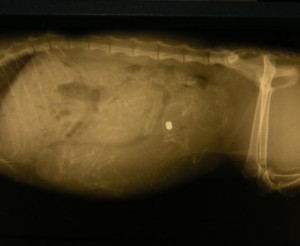

Minulý týden krom rýmy doma byl ve znamení kočiček z České Třebové, kontaktovala mě paní Lída z Poličky, že jedna starší paní poskytla v zimě domov dvěma kočičkám, ale už je dále u sebe nemůže mít. Tak jsem se v neděli 8.3. do České Třebové rozjela... Paní je nesmírně milá, ale pro její opravdu vysoký věk není schpna pečovat o 4 kočky (2 jsou její vlastní). Začala jsem kočičkám - Pomněnce a Andulce shánět alespoň provizorní depozitum, když domů je nebylo možné vzít. Paní Hanka z Hradce Králové by je i vzala, ale pouze naočkované. Protože Andulka měla rýmu a zánět dásní, domluvila jsem se s "choceňáky" - tedy ordinací ve Svitavách náležející pod kliniku MVDr. Štancla v Chocni, že kočičky tady ve Svitavách ubytují a Andulku vyléčí. Dcerka mi pro obě kočičky v pondělí zajela a já je předala k ošetření. Andulka dostala injekci na zánět dásní a rýmičku a obě čekal rentgen...výsledek? Andulka dobrý, Pomněnka krom broku v boku čeká 3 koťátka...

rentgen miminek